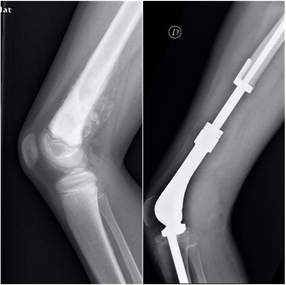

Tumores malignos

Los sarcomas óseos son tumores óseos muy infrecuentes, con una incidencia aproximada de 1 caso por cada 100.0000 habitantes. El Osteosarcoma es el tumor óseo primario maligno más frecuente en la infancia, seguido por el el Sarcoma de Ewing. En las radiografías se suelen evidenciar lesiones líticas, permeativas, con destrucción ósea, reacción perióstica y afectación del los tejidos blandos cercanos. Estos pacientes ,además de dos proyecciones radiográficas, precisarán estudios complementarios de imagen, biopsia, estudio de extensión para descartar diseminación pulmonar, y valoración multidisciplinar. La cirugía oncológica de salvamento de extremidad y reconstrucción es la técnica de elección.

Los sarcomas óseos son tumores primarios malignos muy raros que afectan fundamentalmente a niños y adolescentes, aunque también puede aparecer en pacientes mayores de 65 años, en relación con otras enfermedades o radioterapia. Debemos sospechar la presencia de un tumor maligno primario de hueso en pacientes con imágenes radiológicas de apariencia agresiva, como márgenes mal definidos, lesiones líticas con patrón permeativo, destrucción de las corticales, reacción perióstica e invasión de los tejidos blandos. Si detectamos una lesión de este tipo debemos siempre realizar una valoración multidisciplinar por equipos especializados en Traumatología oncológica y Oncología.